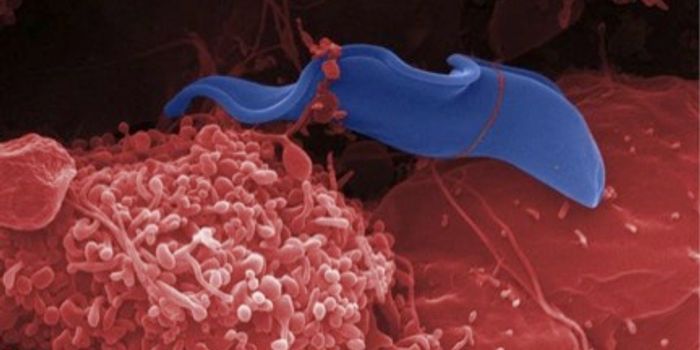

MAY 24, 2017MicrobiologyChagas disease causes an initial period of infection only lasts a few months, or so it was thought.